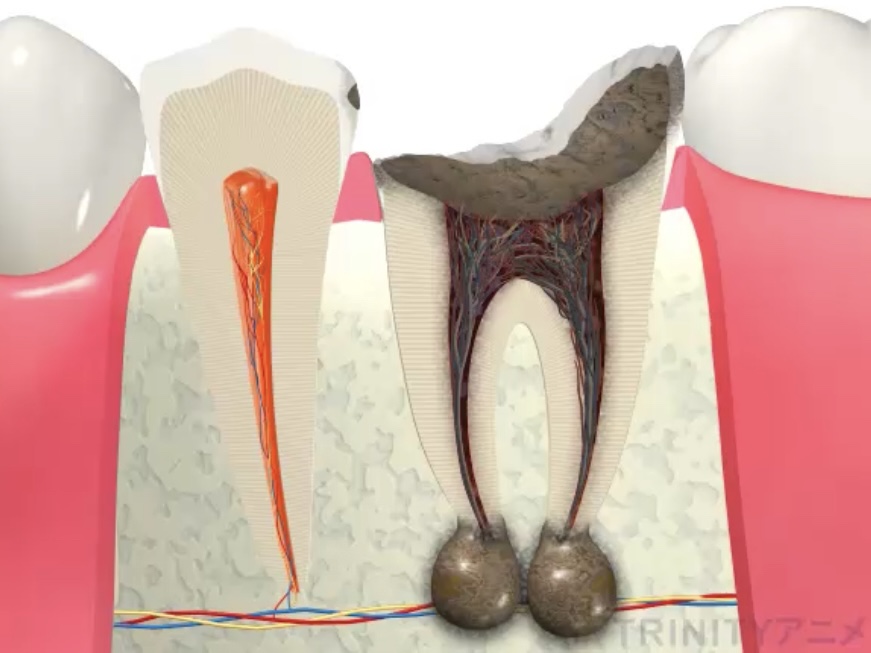

神経ギリギリまで虫歯が存在した場合、虫歯自体はしっかり取り切っていても、虫歯の菌がすでに神経内部に侵入してしまっている可能性があります。

そうすると神経が菌に感染しダメになってしまいます。

この状態になっていると神経を取る治療、根管治療が必要になります。